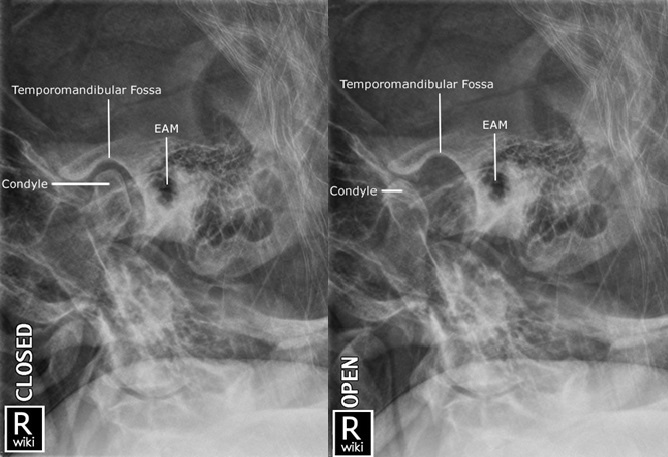

4. TMJ Radiography

1) Adult Lateral Oblique - Closed/Open Mouth